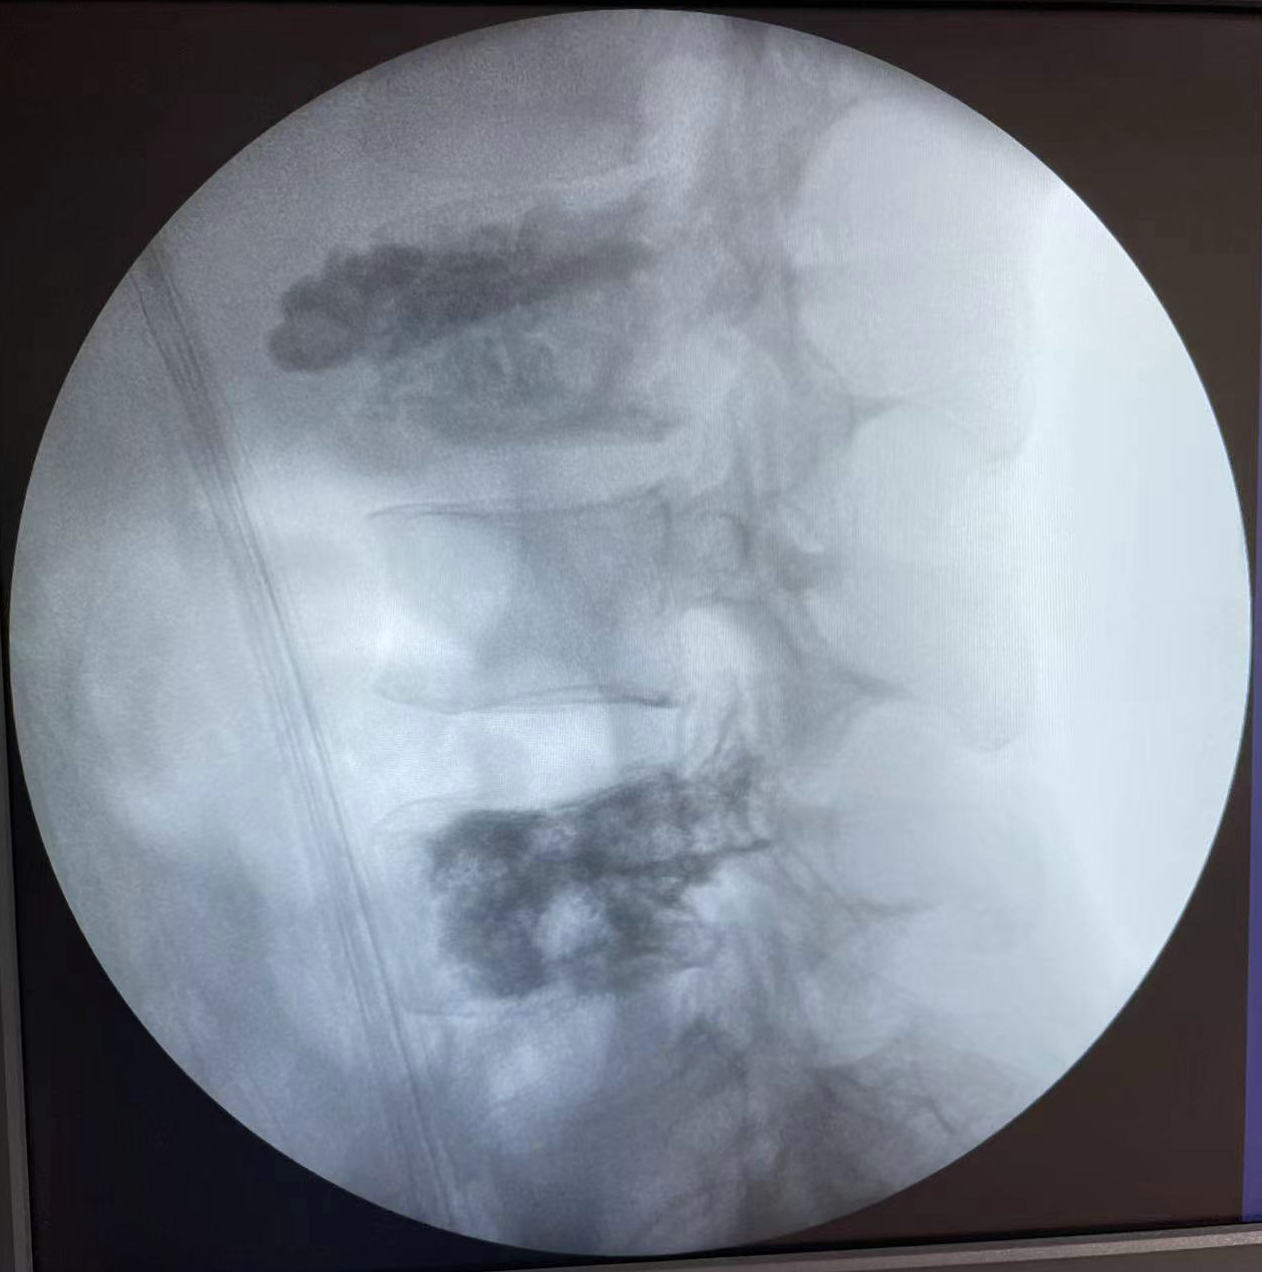

术中微波消融情况